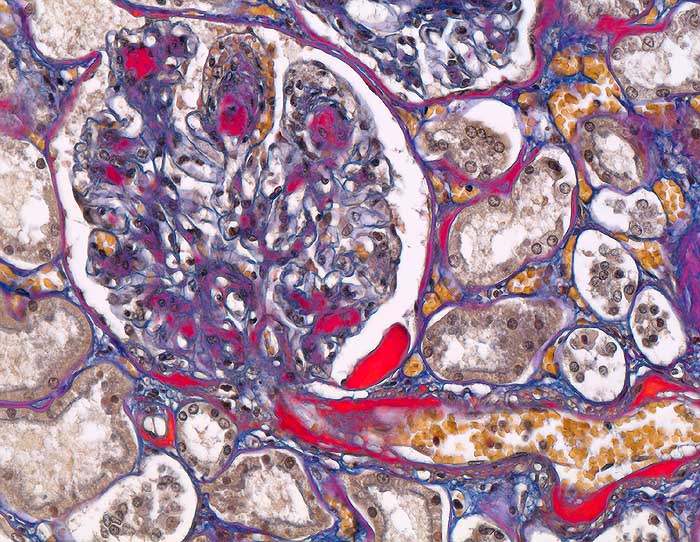

Im allgemeinen ist die Niere infolge von Glomerulumhypertrophie und Tubulushyperplasie vergrössert und derb, die Oberfläche ist granuliert. Bei schwerer Atherosklerose und fortgeschrittener Niereninsuffizienz kann die Niere auch normal gross oder verkleinert sein. Die Kombination von nodulärer Glomerulosklerose, hyalinen Schlingenkappen (=Proteinthromben in den Glomerulumschlingen (> 1916)) oder Kapseltropfen (> 1907) und Arteriolosklerose in Vas afferens und efferens ist beweisend für eine diabetische Nephropathie. Jede einzelne Läsion für sich genommen ist aber unspezifisch. Eine noduläre Glomerulosklerose kann auch vorkommen bei membranoproliferativer Glomerulonephritis (> 2652), Leichtkettenglomerulopathie oder Amyloidose (> 2019). Der nodulären Glomerulosklerose geht bei Diabetikern eine diffuse Glomerulosklerose (> 1906) voraus. Dabei zeigen die glomerulären Basalmembranen und das Mesangium eine progrediente gleichförmige Verbreiterung. Bei der nodulären und diffusen Glomerulosklerose handelt es sich aber wahrscheinlich um zwei pathogenetisch unterschiedliche, sich überlagernde Krankheitsbilder. Typisch bei Diabetikern ist im Unterschied zur arteriellen Hypertonie die Arteriolosklerose von Vas afferens und efferens (> 1911) und oft auch der Vasa recta. Intrarenale Arterien können eine Atherosklerose mit Atheromen zeigen. Subendotheliale Proteinablagerungen teilweise mit Verschluss der Glomerulumschlingen (Schlingenkappen) und knotige Proteinablagerungen in der Bowman'schen Kapselbasalmebran (Kapseltropfen) gehören zu den sogenannten exsudativen Läsionen (> 1919) (> 1920) der diabetischen Nephropathie und führen zu Synechien sowie zur globalen Glomerulosklerose. Gleichzeitig mit den Glomerulumveränderungen treten tubuläre Basalmembranverbreiterungen auf, später eine Tubulusatrophie und interstitielle Fibrose mit Begleitentzündung. Auch die Basalmembranen der peritubulären Kapillaren sind verdickt.

• Verbreiterung des Mesangiums mit Ausbildung von Knoten(noduläre Glomerulosklerose).

• Exsudative Läsionen: Hyaline Schlingenkappen (Proteinthromben in Glomerulumschlingen, im virtuellen Präparat nicht sichtbar) und Kapseltropfen (Proteinablagerungen im Bowman’schen Kapselraum).

• Arteriolosklerose von Vas afferens und efferens (Gefässwandhyalinose durch Ablagerung von Plasmaproteinen und Lipiden in der Gefässwand).

• Intrarenale Atherosklerose.

• Verdickte Basalmembranen der peritubulären Kapillaren.

• Verbreiterung der tubulären Basalmembran.

• Tubulusatrophie mit interstitieller Fibrose und Begleitentzündung.